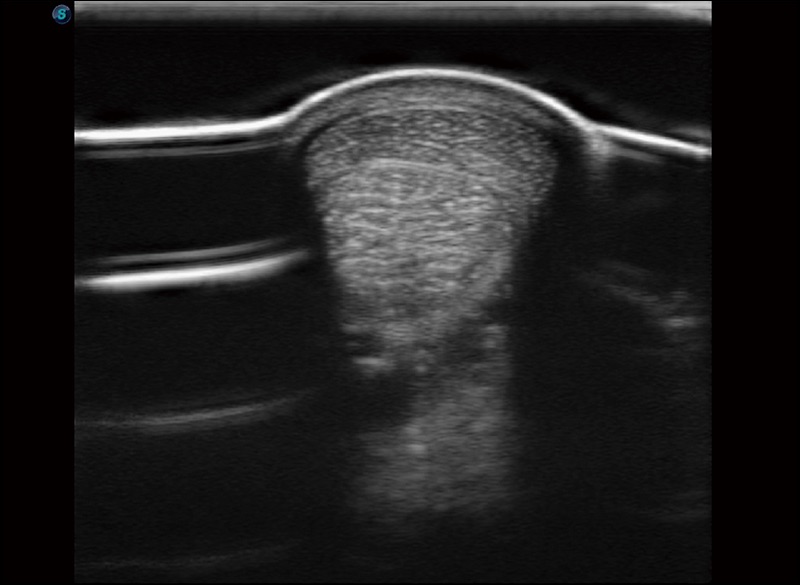

穿刺针增强

高清显示穿刺进针情况